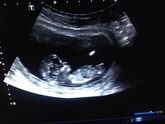

Девчули, милые. Скажите пожалуйста какие вы делаете скрининг 1,2,3 обычный или в3,4 д?